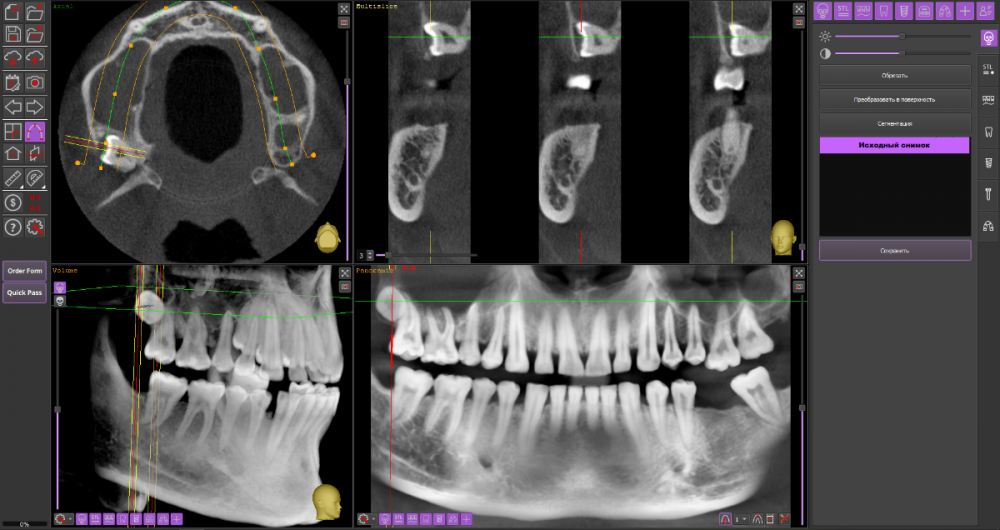

Mnrg Опубликовано 6 июля, 2023 Поделиться Опубликовано 6 июля, 2023 Всех приветствую! Беспокоит правосторонний гайморит и тонзиллит. Сделали КТ, нашли восьмерку, но предложили вместо удаления восьмерки депульпировать шестерку, консилиум сошелся во мнении, что корень перфорирует пазуху и пломба слишком близко к нерву, возможно воспаление. При зондировании между 6 и7 слегка побаливает десна, шестерка не беспокоит, холод чувствует, но не болит. Восьмерку предложили оставить. Спорить не стал, лишь решил собрать воедино мнения специалистов, т.к ближайшие более менее нормальные клиники от 100км. Архив с файлами КТ прикрепил, прошу специалистов глянуть и поделиться мнением, с чего все-таки начать, помочь разобраться.Archive.rar Ссылка на комментарий

wladdX Опубликовано 7 июля, 2023 Поделиться Опубликовано 7 июля, 2023 (изменено) Гайморит у вас совершенно необязательно имеет одонтогенную природу (вызван зубами). Судя по КТ, зуб 16 может быть виновником (а может и не быть). Для уточнения нужна также проверка витальности его пульпы (жив нерв или нет). Если пульпа нежизнеспособна, то этот зуб почти наверняка поддерживает воспалительный процесс в пазухе. Зуб 18 вряд ли нужно трогать. Лежит он себе в кости и пускай, никому он там не вредит. Да он вплотную прилежит к корням зуба 17, но и только. С внешней средой не контактирует. Никакого негативного влияния на соседние зубы он оказывать не должен: формирование корней завершено, потенции к росту и какому-либо движению нет. Удаление зуба 18 в данной ситуации вряд ли оправдано. Процедура не самая простая, но и не запредельной сложности. Изменено 7 июля, 2023 пользователем wladdX Ссылка на комментарий

Mnrg Опубликовано 7 июля, 2023 Автор Поделиться Опубликовано 7 июля, 2023 6 минут назад, wladdX сказал: Гайморит у вас совершенно необязательно имеет одонтогенную природу (вызван зубами). Судя по КТ, зуб 16 может быть виновником (а может и не быть). Для уточнения нужна также проверка витальности его пульпы (жив нерв или нет). Если пульпа нежизнеспособна, то этот зуб почти наверняка поддерживает воспалительный процесс в пазухе. Зуб 18 вряд ли нужно трогать. Лежит он себе в кости и пускай, никому он там не вредит. Да он вплотную прилежит к корням зуба 17, но и только. С внешней средой не контактирует. Никакого негативного влияния на соседние зубы он оказывать не должен: формирование корней завершено, потенции к росту и какому-либо движению нет. Удаление зуба 18 в данной ситуации вряд ли оправдано. Процедура не самая простая, но и не запредельной сложности. Шестерку проверяли холодом - чувствует, не знаю, означает ли это жизнеспособность пульпы, но на холод реагировал немного сильней других зубов. Сегодня открыл КТ программой RadiAntViewer и обнаружил в 3D просмотре визуальные признаки нахождения части восьмерки в краю пазухи. Конечно я не могу утверждать, т.к не врач и насколько понимаю это режим моделирования, но все же выглядит убедительно на мой скромный взгляд. Еще один глупый вопрос, если позволите) Возможно ли в шестерке в одном из трех корней воспаление и нерв разрушен, а другие два при этом будут создавать чувствительность, т.е быть "живыми" или же это фантастика? Деньги запросили немалые для нашего региона за депульпацию (13к) поэтому пытаюсь собрать как можно больше информации прежде, чем принимать решения. Ссылка на комментарий

wladdX Опубликовано 8 июля, 2023 Поделиться Опубликовано 8 июля, 2023 Ничего нового добавить к своим словам я не могу. Разве что повторить : "Гайморит у вас совершенно необязательно имеет одонтогенную природу". Т.е. надо рассматривать возможность ЛОР-патологии в чистом виде. Если зуб 16 с живой пульпой, то других одонтогенных причин при помощи данного КТ исследования я не вижу. На истину в последней инстанции не претендую. 1 1 Ссылка на комментарий